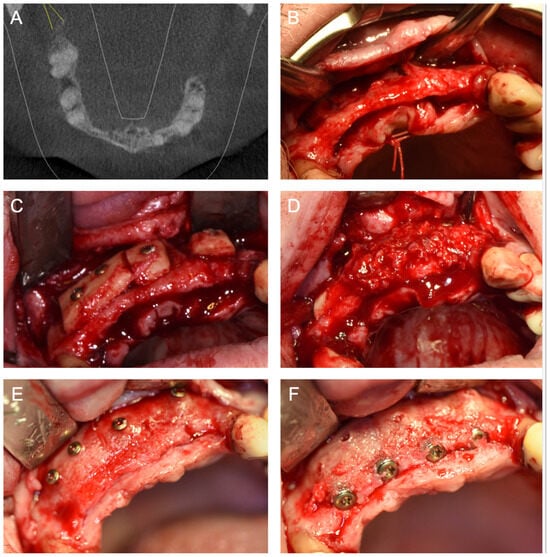

- ICG—Autogenous bone block harvested from the iliac crest and fixed with titanium screws (Figure 1).